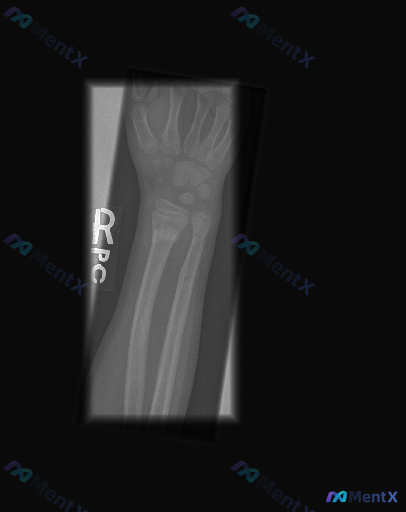

青少年右腕外伤后X光未见明确骨折,但这真的等于“无异常”吗?

- 骨骼发育:桡骨、尺骨远端可见明显骺板(生长板),骨骺尚未完全融合;

- 骨折/脱位:桡骨远端、尺骨远端、腕骨均未见明确骨折线、皮质中断或明显脱位征象,干骺端形态规整;

- 关节对位:桡腕关节、下尺桡关节对位良好,间隙清晰;腕骨排列整齐;

- 骨密度与软组织:骨皮质连续,骨密度在正常范围内;腕周软组织轮廓大致正常,未见明显肿胀或异物影。

右腕正位片显示骨骼结构完整,未见明确骨折及脱位征象;受检者仍处于生长发育期(骨骺未闭合)。

📋答案:结合完整资料,最后更能成立的方向是:首先警惕隐匿性Salter-Harris I/II型骨骺损伤,建议MRI或严格制动后复查。